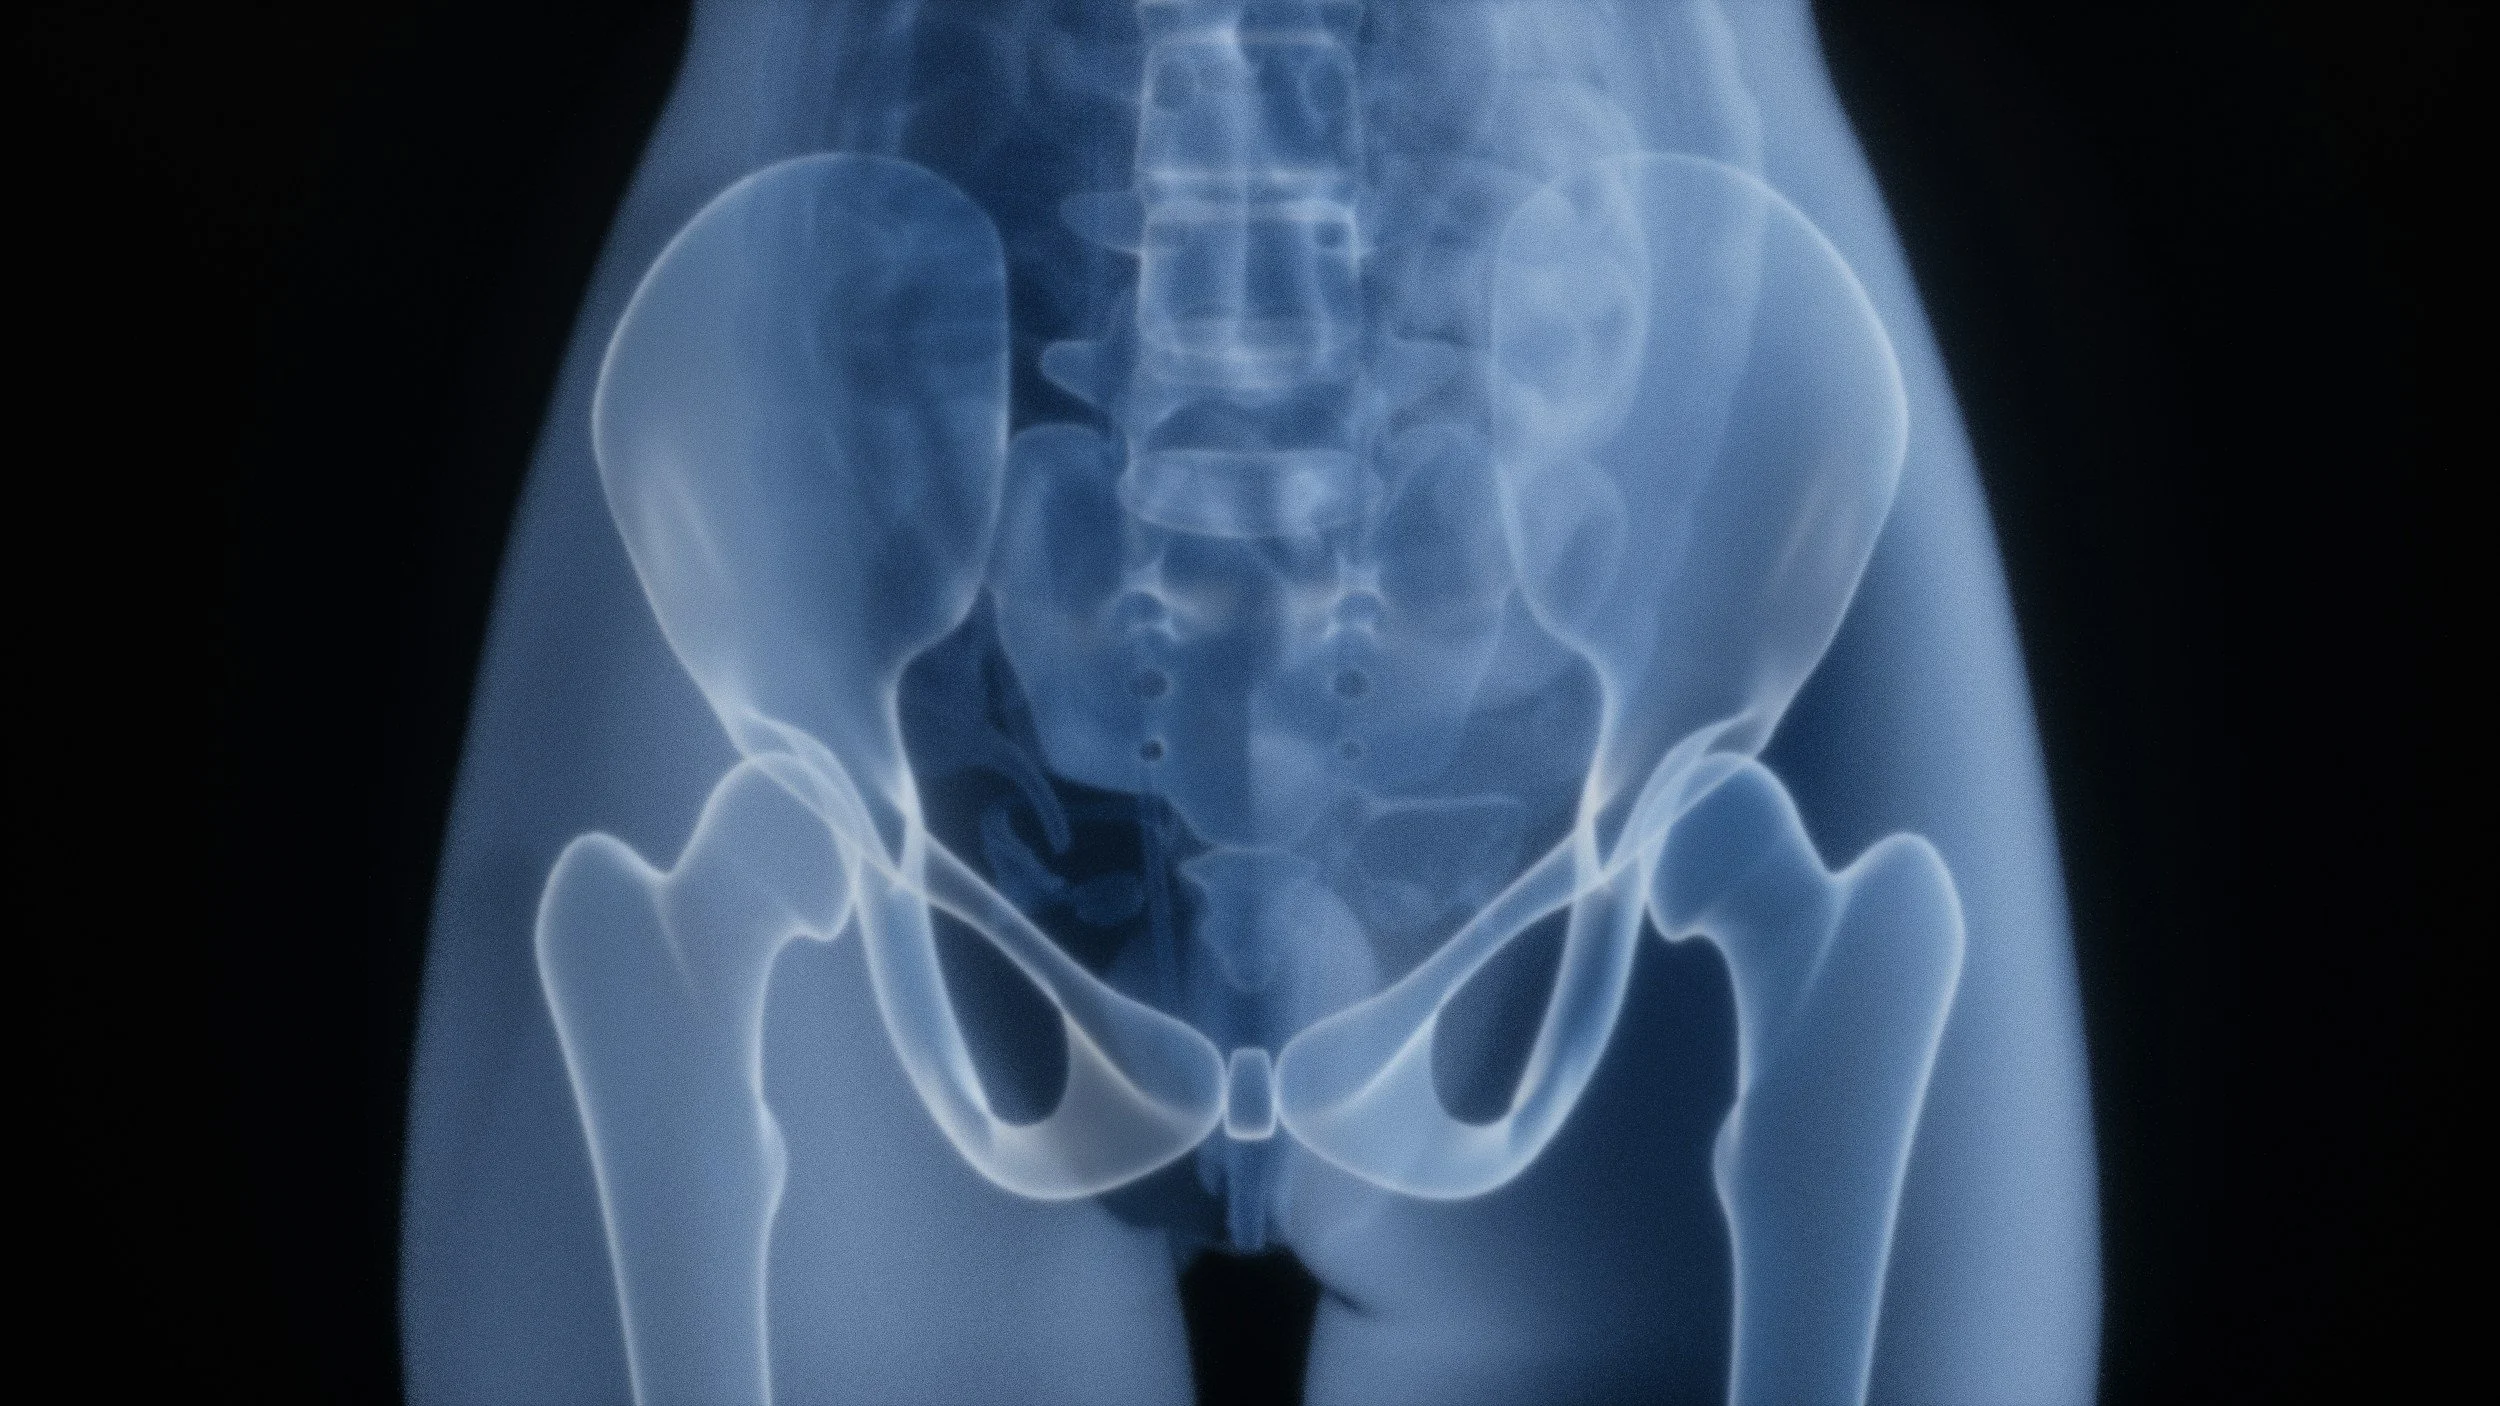

10 Everyday Habits That Can Keep Your Pelvic Floor Tight (And What To Do Instead)

Chronic pelvic floor tension isn’t just about exercise—it’s shaped by daily habits like breathing, posture, and bathroom patterns. Learn what might be keeping your pelvic floor tight and how to fix it.